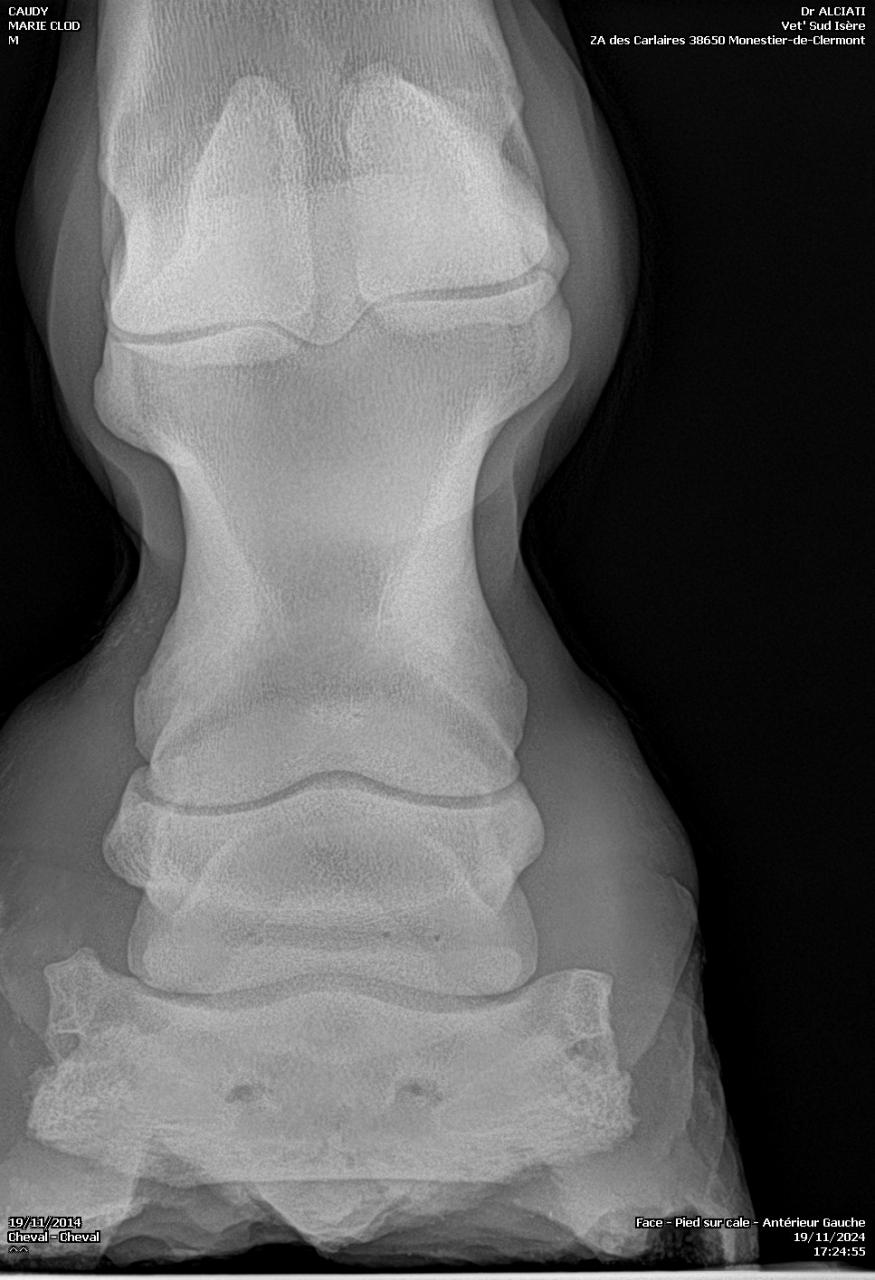

Bascule 3ème phalange qui appuie sur la sole

| Dire merci | Je fais un sujet à part pour donner des nouvelles ![]() J’ai fait passer un autre véto pour un 2ème avis. Au début il pensait à un abcès très profond, emplacement détecté avec la pince à sonder. Il a ensuite fait des radios : si j’ai bien compris, la 3ème phalange appuie sur la sole Il y a également de l’arthrose ... Le traitement pour le moment : anti inflammatoires et hipposandales en attendant de pouvoir referrer, et changer de maréchal ferrant. Apparemment il existerait un traitement au laser, le véto va se renseigner. Cody a fait une fourbure l’année dernière, des radios ont été faites à ce moment. J’ai aussi refait des radios de contrôle cette année, il restait une légère bascule de P3. |

| Dire merci | Il y a quand même de jolies bascules, il doit pas être bien c'est sûre. Les degrés de bascule t'ont été donnés? Pour moi il y a urgence à trouver un bon maréchal, qui va travailler avec les radios, mais ça va mettre plusieurs mois à "rentrer dans l'ordre" si pas d'autres crises inflammatoires et nouvelles bascules, ça se compte en plusieurs mois voir année. Et malheureusement une surveillance constante. |

| Dire merci | J'ai eu le collègue du véto au téléphone : pas de risque immédiat que la phalange perce la sole il reste 1 cm. La 3ème phalange appuie sur la sole, il y a nécrose. La pointe ne risque pas de casser. Je viens de commander 2 hipposandales Cloud. Il faut que je trouve quelqu'un pour déferrer Cody et éventuellement parer l’autre antérieur. Message édité le 22/11/24 à 20:31 |

DéconnectéDire merci | pas de risque immédiat que la phalange perce la sole il reste 1 cm. Bien optimiste ce véto car tant que le pied reste ferré donc en support périphérique plutôt que le poids soit porté par toute la sole une descente peut aller très vite. C'est une logique mécanique. |

| Dire merci | dejavu Merci pour cette explication. L'antérieur gauche a été déferré et j'ai commandé des hipposandales Cloud conçues pour limiter la bascule. Je cherche un professionnel compétent près de Grenoble. |